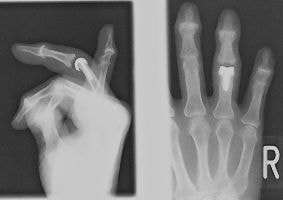

槌指(つちゆび)・マレットフィンガー

末節骨骨折・伸筋腱断裂・スワンネック変形

Mallet Finger

マレット変形

スワンネック変形

末節骨裂離骨折の経皮ピンニング

槌指とは木槌(マレット)のように変形した指を指す言葉であり、これには、末節骨の伸筋腱が付着する部位の裂離骨折によっておこるものと、伸筋腱の終止腱の断裂によっておこるものが含まれます。

いずれの場合も、症状はDIP関節の自動伸展障害ですが、放置するとスワンネック変形(白鳥の首様の変形)を生じます。さらに、骨折の場合には早期にDIP関節の変形性関節症を生じる原因となることがあります。

治療は、骨折があれば骨片の整復・固定を行うことで良好な結果が得られます。腱断裂の場合には2ヶ月間の外固定により4割の指に良好な結果が得られますが、6割の指には様々な程度(5〜20°)のDIP関節伸展障害が残存します。結果は、どれだけ早期に固定を開始できたか?と、どれだけしっかりとDIP関節の伸展位固定を維持できたか?にかかっており、ただ単に固定していたら治る、というものではありません。

陳旧例で骨の変形癒合がある場合には、骨切術により変形の矯正が可能です。腱断裂の陳旧例では、手術による腱の縫縮あるいは腱移行術によって変形の矯正が図られます。

腱性槌指のスプリント固定の一例

末節骨変形治癒骨折の骨切術(左:術前・右:術後)